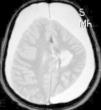

Ingresa en nuestro centro a los 7 años de edad, por presentar varias crisis tónico-clónicas que afectan principalmente al hemicuerpo derecho, con pérdida de fuerza posterior a este nivel. En el TC craneal al ingreso se observaron lesiones hipodensas a nivel parafalcial anterior izquierdo y fronto-parietal izquierdo y en la RM cerebral lesiones córtico-subcorticales a nivel frontal superior, frontal medio y parietal, de aspecto tumefactivo y atrofia marcada del hemisferio cerebral izquierdo (figs. 1 y 2). No se apreciaron alteraciones en el árbol vascular. En el EEG presentaba asimetría interhemisférica con gran lentificación en el hemisferio izquierdo y actividad paroxística focal con ondas agudas, puntas y complejos punta-onda de elevado voltaje, principalmente a niveles frontal y fronto-temporal izquierdos. La ecografía Doppler de troncos supraórticos no mostró alteraciones. Se solicitaron estudios de laboratorio, incluyendo estudio metabólico completo y serologías virales, todos ellos anodinos. La citoquímica de líquido cefalorraquídeo (LCR) fue normal y las PCR de virus neurotropos en LCR negativas. Tampoco se apreciaron células malignas. Otros estudios de inmunología realizados comprenden anticuerpos onconeuronales, negativos; ANA 1/80 patrón moteado, y anti-RNP-A positivo. Como pruebas de segundo nivel solicitamos RM cerebral con espectroscopia que mostró varias lesiones córtico-subcorticales, alteraciones en el cociente N-acetilaspartato/colina e inversión en el cociente de lípidos/lactato, sin demostrarse aumento de lactato en el LCR. Otros estudios llevados a cabo: fondo de ojo, estudio cardiológico, audición, biopsia de piel y de músculo, resultaron normales. Los potenciales evocados visuales no resultaron alterados y en los potenciales evocados somatosensoriales se encontraron anomalías en la vía somatosensorial procedente de ambas extremidades superiores, con respuesta cortical de amplitud reducida bilateralmente. Bajo la sospecha de síndrome de Rasmussen se envía a hospital de referencia, donde realizaron nueva RM cerebral (secuencias DWI, T1, DP-T2, FLAIR, T1D3) con aumento de surcos corticales y pérdida de volumen del hemisferio cerebral izquierdo, compatible con esta enfermedad.